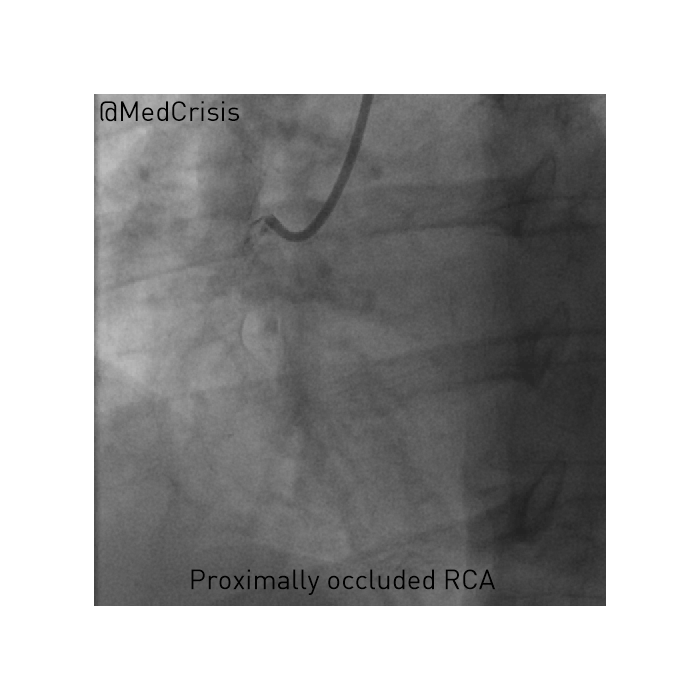

She was still in pain on arrival at the interventional centre and transferred immediately to the cath lab. Her left system showed moderate disease in the circumflex artery. However, as expected, the acute problem was her right coronary artery, which was occluded.

Below you can see the guide catheter engaged with the blocked right coronary artery and no flow is getting past the clot.